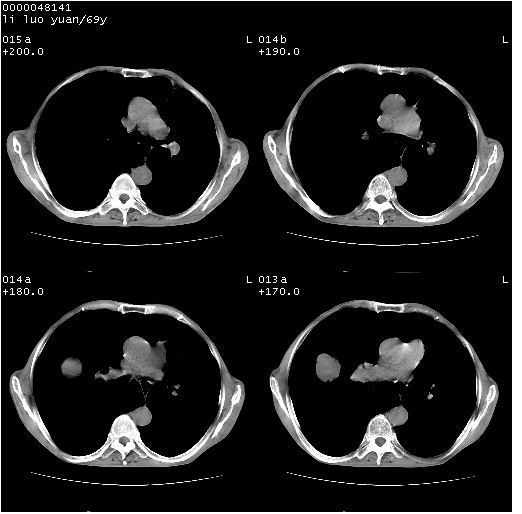

临床资料:老年患者,咯血、消瘦

影像表现:桶状胸,双肺纹理纤细、紊乱,透过度增高,肺野内可见多发、散在、大小不等的无壁高透过影,右肺中叶外侧段分叶样软组织占位,左上肺纤维索条样密度影,相应层面左侧胸腔轻度萎陷,纵隔左移。

影像诊断:1、慢支、肺气肿、双下肺野肺大泡形成

2、左上肺陈旧性肺结核

3、右肺中叶外侧段占位 考虑肺ca可能性较大、建议增强及痰检脱落细胞